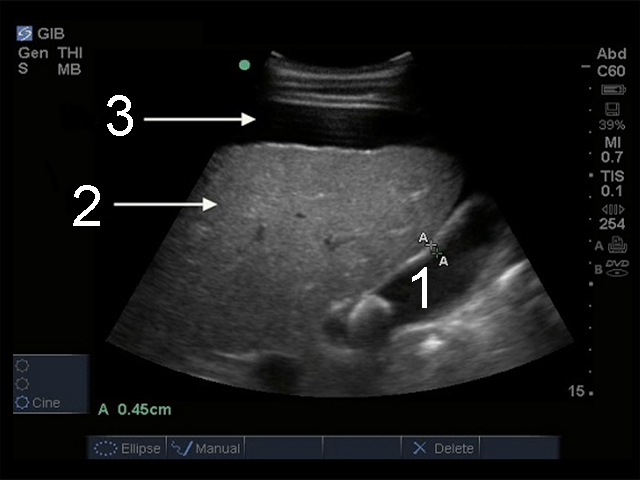

Gallbladder Ascites with Cholelithiasis Image

Gallbladder

Liver

Free Fluid